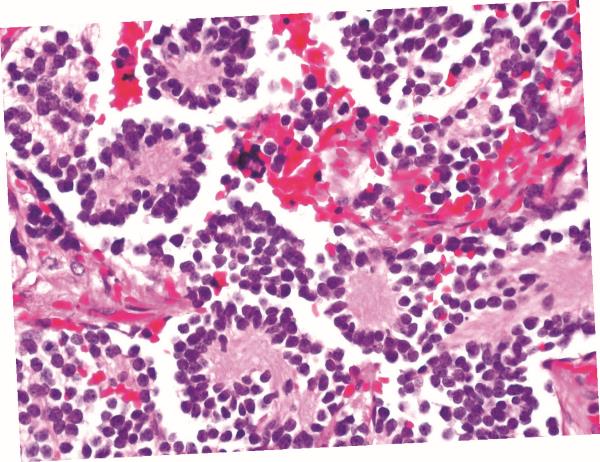

Розетки Гомера Райта, заполненные розовым микроволокном, – нейробластома надпочечников.

В какой-то степени Гомер Райт обнаружил «свои» розетки случайно. В 1910 году он описал в «Журнале экспериментальной медицины» серию из двенадцати опухолей (которые тогда считались саркомами) с особой микроскопической структурой – тканью, созданной маленькими круглыми клетками. Сегодня мы выделяем целую категорию раковых заболеваний, состоящих из маленьких синих клеток (из-за клеточного ядра, которое занимает большую часть клетки), и они по-прежнему остаются настоящим бичом для патологов. И все же давайте вернемся к Джеймсу Гомеру. Структуры, которые он наблюдал в своих препаратах, заставили его поверить, что на самом деле он имеет дело с новообразованиями не из соединительной ткани, а из очень примитивных нервных клеток. Скопления маленьких темных клеток, свернутые в розеточные шарики и трубочки, срезанные, повернутые внутрь чащей розовых фибрилл, напомнили ему процессы развития эмбриональной нервной системы – это впечатление оказалось настолько сильным, что он последовал ему и назвал свою статью «Нейроцитома или нейробластома, неочевидные разновидности опухоли». Таким образом, нейробластома оказалась порождением предполагаемой саркомы, а розетки или псевдорозетки и предполагаемые розетки запомнились Райту из-за отсутствия в них просветов (они были фактически забиты волокнами, которые на самом деле являются выступами нервных клеток), и последующие публикации охотно связывали его имя с описанным изображением. По сей день розетки часто появляются в учебниках и экзаменационных вопросах, они также все еще полезны в диагностике, будучи характерными не только при нейробластомах, но и при других примитивных новообразованиях нервного происхождения, например медуллобластома или исключительно редкая и чрезвычайно опасная пинеобластома (pineoblastoma), развивающаяся из клеток шишковидной железы, крошечной эндокринной железы длиной всего несколько миллиметров, которая, может быть, ассоциируется у вас с мелатонином.